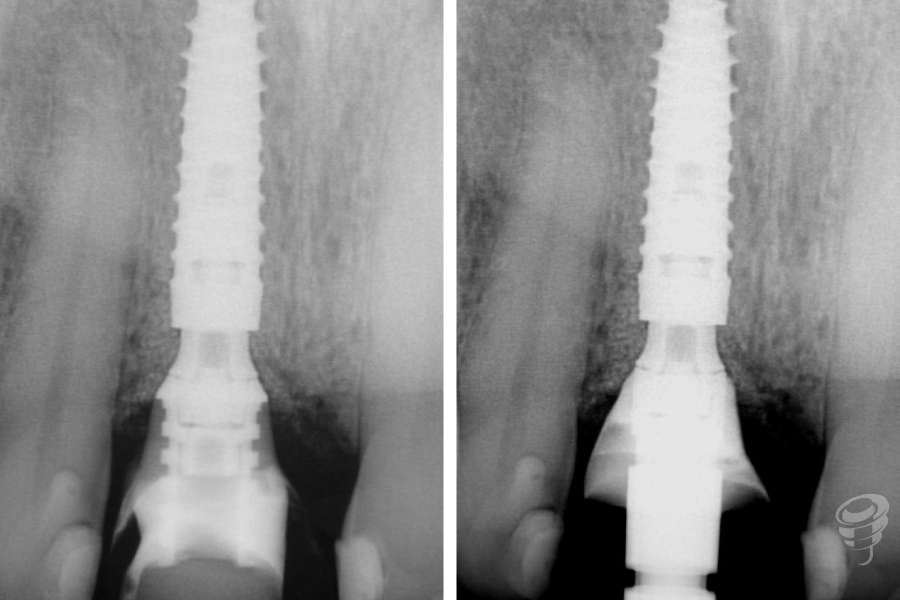

- Colocación del implante: Implante cónico de titanio grado IV (IPX 4012) con torque de inserción de 40 Ncm. Posición: 3mm apical al CEN del diente adyacente, 2mm palatino a la tabla vestibular.

- Confirmación de osteointegración (ISQ > 70).